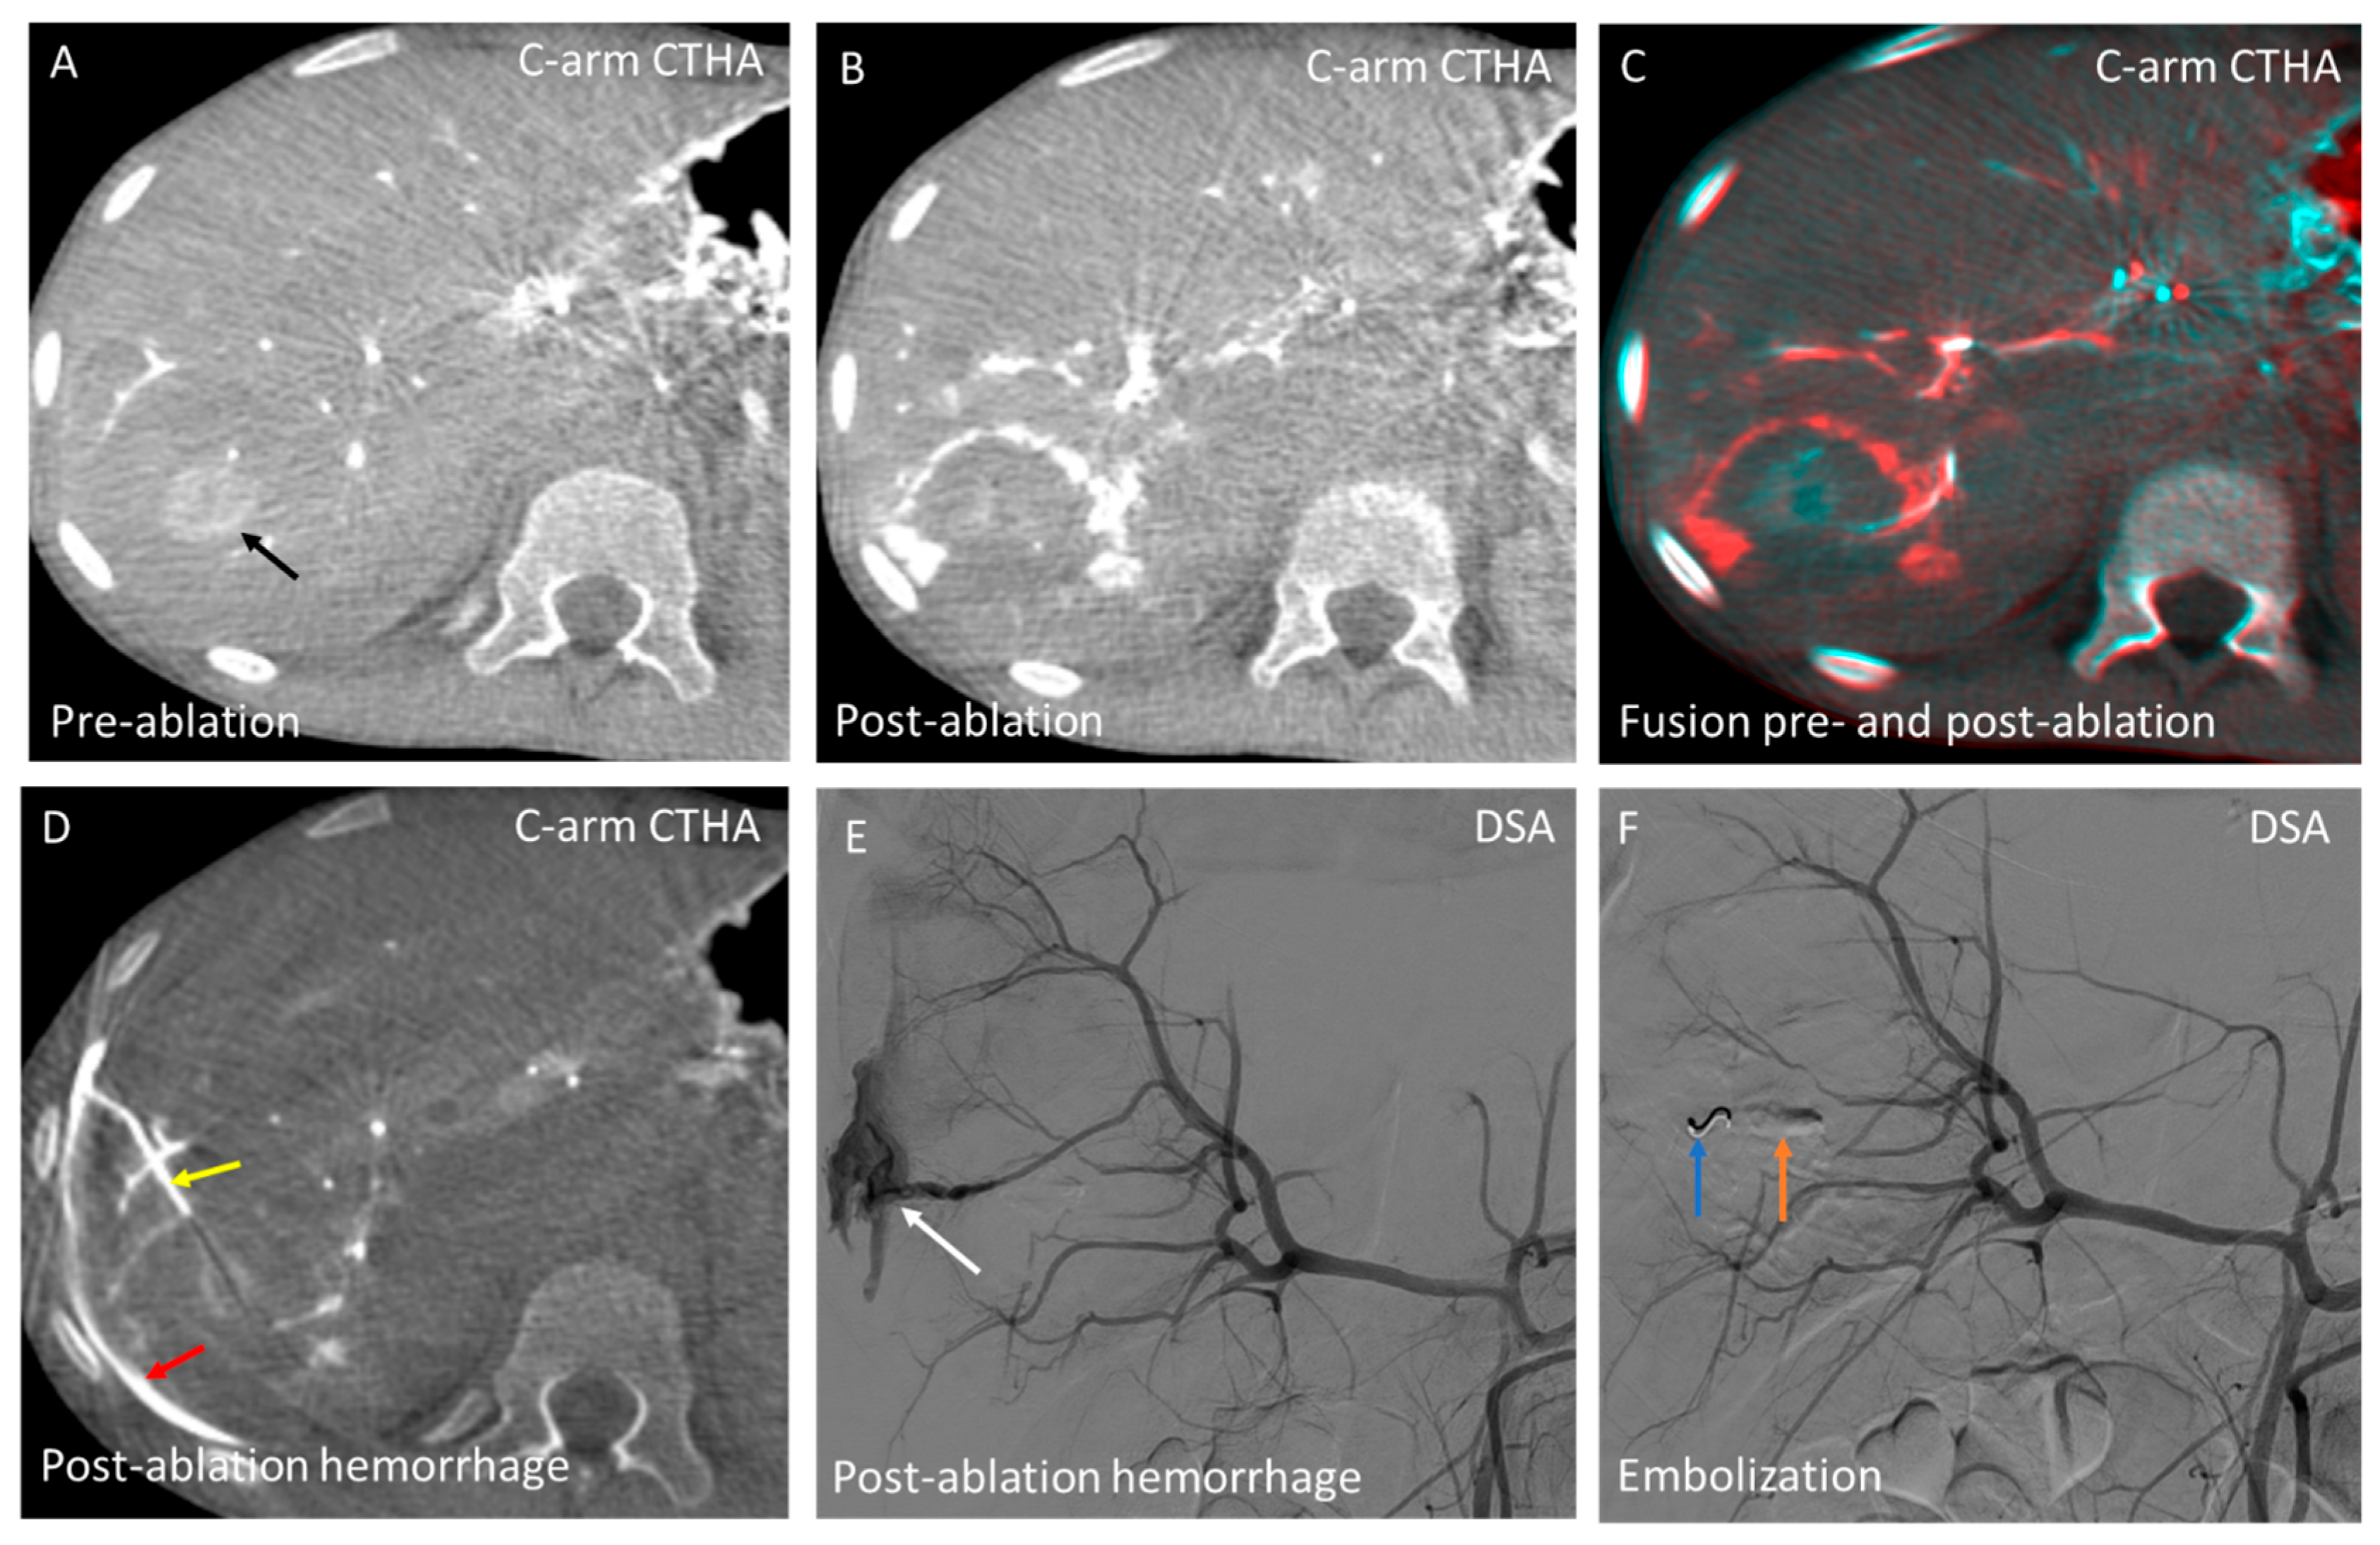

3.4. Domain D—Hemorrhage Control